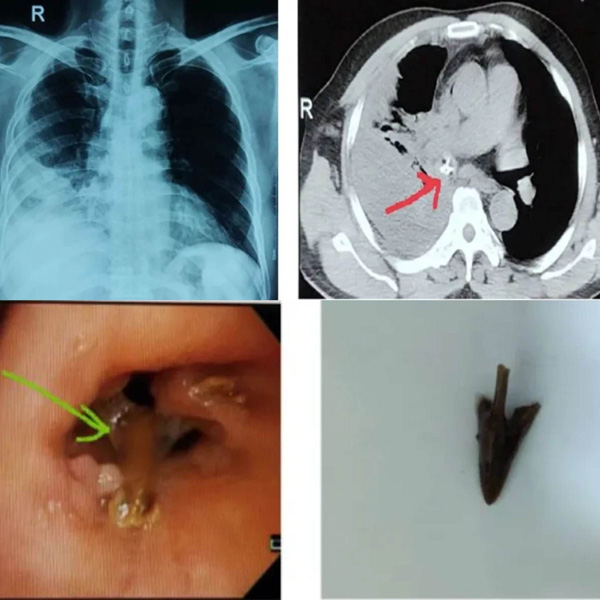

Bệnh viện Quân y 103 (Hà Nội) vừa cho biết mới điều trị thành công ca dị vật phế quản phức tạp, bệnh nhân vào viện sau 1 tháng bị sặc mảnh mỏ gà có kích thước lớn gây nhiều tổn thương.

Bệnh nhân là người đàn ông 55 tuổi ở Hà Nội, vào Trung tâm Nội hô hấp của bệnh viện do nhiễm trùng hô hấp kéo dài. Trước khi vào bệnh viện khoảng 1 tháng, bệnh nhân bị sặc khi đang ăn thịt gà. Sau sặc, bệnh nhân đau ngực phải âm ỉ, dai dẳng, đau ngực kèm theo sốt và khó thở tăng dần.

Người đàn ông này tự dùng thuốc giảm đau, hạ sốt tại nhà nhưng triệu chứng đỡ ít, đi khám phát hiện tổn thương đông đặc thùy dưới phải, tràn dịch khoang màng phổi phải.

Các bác sĩ Bệnh viện Quân y 103, cho biết bệnh nhân được chẩn đoán có dị vật phế quản thùy dưới phổi phải biến chứng viêm phổi dưới chít hẹp, kèm theo tràn dịch màng phổi phải.

Bệnh nhân được điều trị kháng sinh tích cực. Khi tình trạng nhiễm trùng ổn định, bệnh nhân được nội soi phế quản ống mềm, phát hiện dị vật là mảnh mỏ gà có kích thước lớn, hình dạng 3 cạnh thành sắc trong lòng phế quản thùy dưới phổi phải, một cạnh găm vào thành phế quản.

Dị vật cũng khiến niêm mạc phế quản xung quanh phù nề, xung huyết mạnh, dễ chảy máu và tổ chức hạt bao phủ, gây chít hẹp gần hoàn toàn phế quản thùy dưới phổi phải.

Kíp nội soi đã tiến hành cắt một phần tổ chức hạt, lấy dị vật ra khỏi phế quản. Sau thủ thuật, bệnh nhân tiếp tục dùng kháng sinh, chống viêm tại chỗ. Quá trình điều trị của người đàn ông này mất 1 tuần.